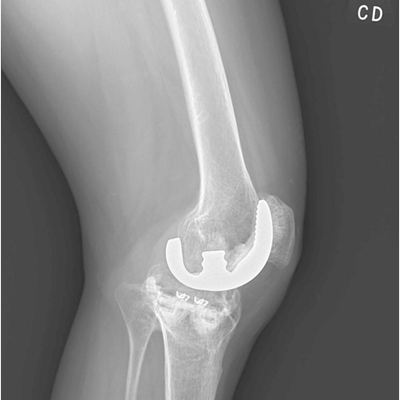

Click on an image below to view more info.